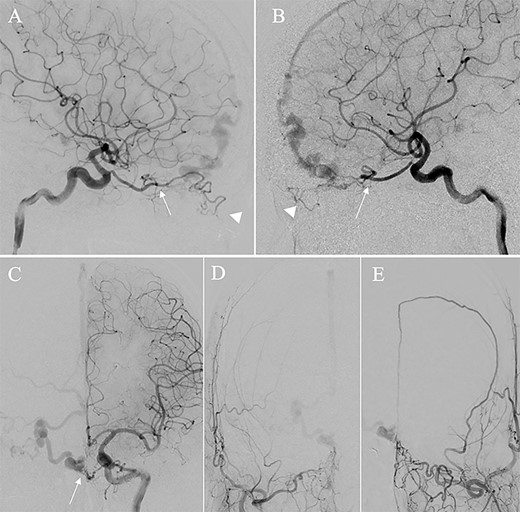

A patient in their 70s with extracranial lymphoma was incidentally found to have ACF–dAVF via head computed tomography and magnetic resonance angiography. Digital subtraction angiography (DSA) confirmed ACF–dAVF with multiple feeding branches, arising from bilateral OphAs, distal IMAs and the left middle meningeal artery (MMA), with cortical venous reflex (Borden type III, Cognard type IV) (Fig. 1). At the patient’s request, we chose endovascular, rather than surgical, treatment. We injected a 20% N-butyl-2-cyanoacrylate (NBCA)–lipiodol mixture into the fistula through bilateral ethmoidal arteries and the left MMA after we placed coils at the terminal branch of the right OphA. However, we could not achieve full penetration into the fistulous connections because of pressure secondary to high flow from the IMA branches, which resulted in incomplete obliteration (Fig. 1). Four months later, we repeated TAE by temporarily reducing nasal blood flow by inserting gauze infiltrated with xylocaine and epinephrine into the nasal cavities. After introducing the guiding catheter, an endonasal surgeon inserted X-ray-detectable surgical gauze infiltrated with 1% xylocaine and epinephrine (1:10 000) into bilateral nasal cavities using a nasal speculum, while paying full attention to avoid damage to the nasal mucosa. Then, we confirmed that the gauzes were placed in appropriate locations in the upper nasal cavity under fluoroscopic guidance. Immediately after insertion, we were able to confirm decreased blood flow from the IMA using DSA (Fig. 2). After this procedure, we navigated a DeFrictor Nano Catheter (Medico’s Hirata, Osaka, Japan) into the terminal branch of the OphA, which was connected to the dorsal nasal artery. Even though there was still a distance from the tip of the microcatheter to the shunt pouch, the NBCA reached the shunt point and penetrated the venous portion (Fig. 3). Follow-up DSA demonstrated complete obliteration of the ACF–dAVF, and blood flow in the nasal mucosa from the IMA branches recovered normally (Fig. 4).

(A) Inserting gauze infiltrated with epinephrine into bilateral nasal cavities. (B and C) Radiograph showing the gauze inserted toward the upper nasal cavity. (D) DSA before inserting the gauze, anteroposterior view, showing blood flow from the right distal IMA. (E) DSA immediately after inserting the surgical gauze, anteroposterior view, showing decreased blood flow from the IMA. (F) Schematic drawing of remaining (red solid line) and occluded feeding arteries (black dotted line) after inserting the surgical gauze. Schema describing that the left dorsal nasal artery (asterisk) remained patent after embolizing the left middle meningeal artery (1), bilateral ethmoid arteries (2) and the right dorsal nasal artery (3), and blood flow from bilateral distal IMAs (4) decreased using our transnasal flow reduction method. (5) Angular artery.